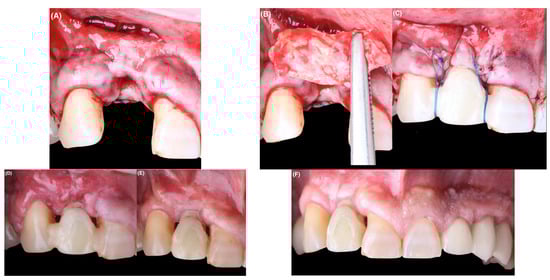

The definitive restoration was delivered 6 months after the second surgery was performed; the soft tissue situation was more favorable in terms of the width and thickness of the keratinized mucosa. For this purpose, a final impression was made using a customized impression hoping to accurately replicate the peri-implant soft tissues achieved after the CTGs were performed []. Regarding the final implant crown material, a customized zirconia abutment was made on a nitrided titanium base (BTI_NU3; BTI, Álava, Spain), adapting the design to the emergence profile already consolidated with the provisional crown (Figure 5A,C). The zirconia used for the abutment had a flexural strength of 1200 MPa (Aidite Zirconia, Hebei, China). The crown was made by CAD-CAM in zirconia with incisal cut-back and layering of veneering feldspathic ceramics for zirconia (Initial, GC Ibérica, Madrid, España). The zirconia used for the cemented crown was a 600 MPa multilayer (3M Lava, Madrid, Spain) to try to get as close as possible to the natural abrasiveness of the antagonist (Figure 5A,D).

Figure 5.

(A): Appearance of the final restoration. (B): Radiographic image 5 months after definitive restoration. (C): Postoperative intraoral view. (D): Clinical view at 4 months of follow-up.

The evaluation of the peri-implant gingival tissues is shown in Table 3. After computing the data from mesial, central and distal points in probing depth, it was observed that the 95% confidence interval of the change after treatment ranged from −1.2–1.0 mm among teeth and −0.7–9.3 mm among treated implants. In a similar way, the average change in gingival recession was −0.9–1.2 mm (CI 95%) for teeth and 0.3–2.7 mm for the implant. This finding revealed that change in the treated implant was significantly greater than among teeth. Regarding change in mucosal thickness, it was observed that since no change occurred among teeth, both keratinized mucosal width and thickness changed from 2 mm to 2.3 mm, respectively, after treatment.

3.2. Esthetic Parameters

Finally, in the final esthetic evaluation, a favorable improvement of 3 points out of 10 was observed in the pink score (PES); specifically, the curvature of the facial mucosa, the vertical level of the facial mucosa, and soft tissue color and texture were improved (Table 2). With respect to the white score, the change was greater than 4 points out of 10 (WES), with a change in all parameters except color, which continued to have a score of 1, meaning that it continued to have a slight discrepancy.